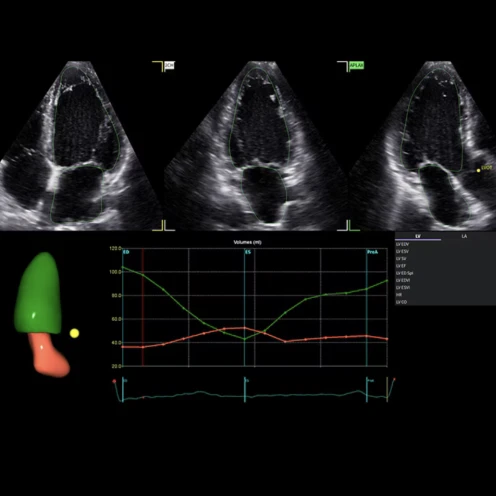

L’ecografo Vivid Pioneer rappresenta la piattaforma ecocardiografica top di gamma di GE HealthCare.

Progettata per offrire qualità d’immagine straordinaria e diagnosi affidabili anche nei casi più complessi. È basato sulla nuovissima architettura cSound Pioneer che aumenta risoluzione spaziale e contrasto in 2D, color flow e 4D, permettendo di visualizzare le strutture anatomiche dettagliatamente anche in pazienti difficili. Introduce nuovi software per l'interventistica e per le analisi volumetriche. Il sistema unisce workflow intuitivo e portabilità elevata grazie alla batteria consentono di spostarlo agevolmente senza interrompere l’attività clinica.